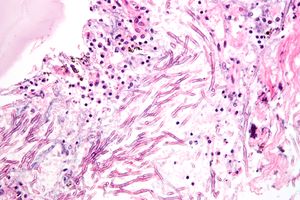

الإمراضية

تسبب العديد من أنواع الرشاشيات أمراض خطيرة في الإنسان والحيوان. ولعل أهم هذه الأنواع هي الرشاشية الدخناء و الرشاشية الصفراء. تنتج الرشاشية الصفراء الأفلاتوكسين والتي تعتبر مسرطنة و سمية في آن واحد. كما أن كل من الرشاشية الدخناء والمقرعية من أهل العوامل المسببة للحساسية. بينما تحمل بقية أنواع الرشاشية أخطاراً إمراضية للنباتات.

داء الرشاشيات

داء الرشاشيات، هو اسم عام لمجموعة من الأمراض التي يسببها فطر الرشاشيات. هذا الفطر، وخلافاً لفطريات المُبْيَضَّة، ليس موجوداً بشكل طبيعي في جسم الإنسان، بل هو موجود في البيئة وينمو على أوراق النباتات والأشجار الميتة، في مستودعات الحبوب، الأسمدة العضوية والخضروات المتعفنة. ويمكن العثور عليها في نبتة الميرحوانا (القنب الهندي).[6]